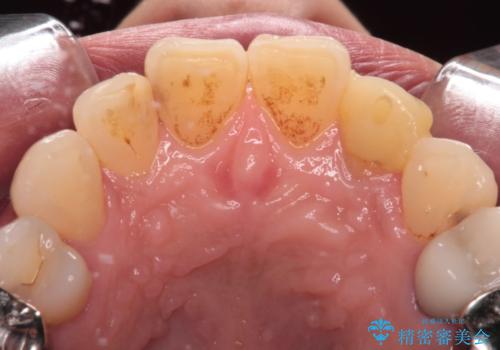

根管治療の土台のまま放置してしまった前歯 オールセラミッククラウンによる補綴治療

- 前歯の根管治療の際に、一時的に見た目を回復したままの状態で放置してしまったとのことで来院された患者様です。

土台の状態は良好であったため、仮歯に置き換えた上でオールセラミッククラウンにて補綴治療を行うこととしました。